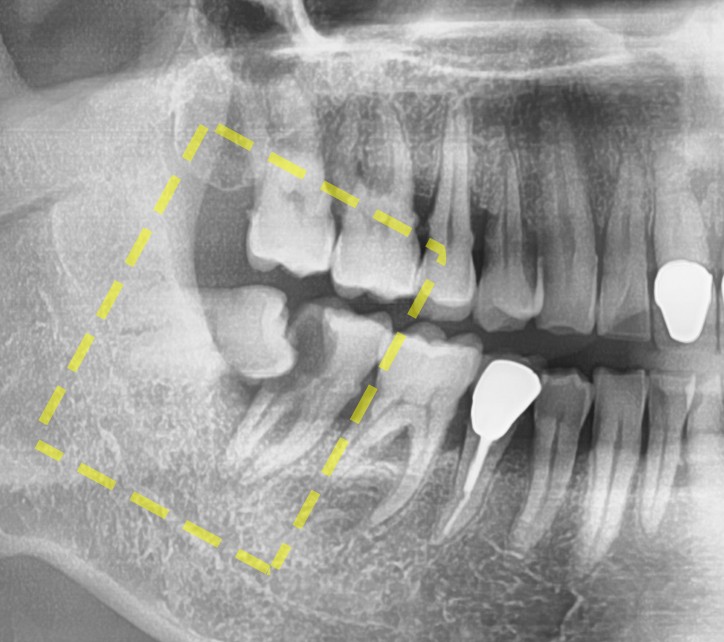

엑스레이를 보면 어디가 문제인지 찾으실 수 있나요?

바로 누워있는 사랑니 와 그 앞에 있는 큰 어금니가 문제가 되겠습니다.

조금 더 해상도 높은 엑스레이를 보여드릴게요.